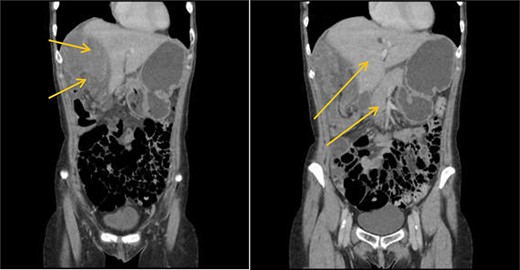

Patient initially diagnosed as biliary colic and surgical team had been contacted. Plain Abdominal radiograph showed dilated small bowels loops (Fig. 1). Chest radiograph revealed air under right hemi-diaphragm (Fig. 2). CT scan was done in emergency department and confirmed interposition of bowel between the diaphragm and the liver with a vascular/mesenteric pedicle swirl suggestive of malrotation or volvulus of the right colon. There was marked mural thickening and bold dilatation with high attenuation mucosa in keeping with closed loop obstruction and possible necrosis (Figs 3 and 4).

CT scan shows interposition of ileum, cecum and ascending colon between liver and diaphragm pushing right loop of the liver and gallbladder medially.